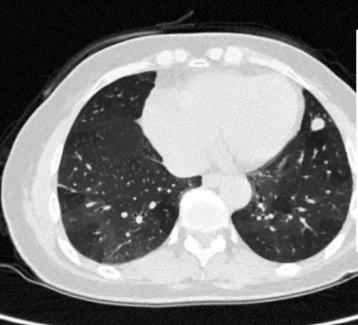

3年前发现双肺斑片结节影, 1个月前复查胸部CT示双肺散在斑片影,左上叶结节较前稍增大

CT示双肺散在斑片结节影,左肺舌段见一结节,直径约1.2cm